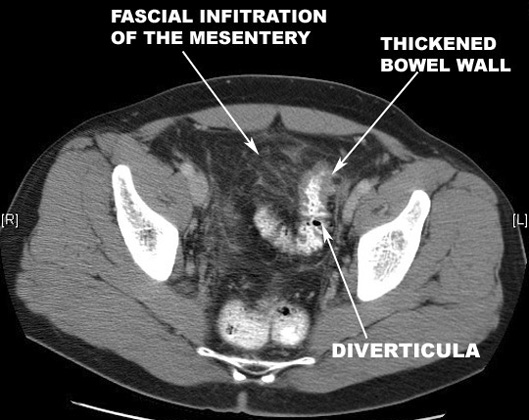

| Diverticula out pouching from colon | Diverticula in lower GI and CT scan |

| Diverticulitis | |

Facial infiltration of mesentery |

Thickened bowel wall |

Inflammatory Mass with air pockets |

CT scan with GI contrast study showing findings of diverticulitis. |